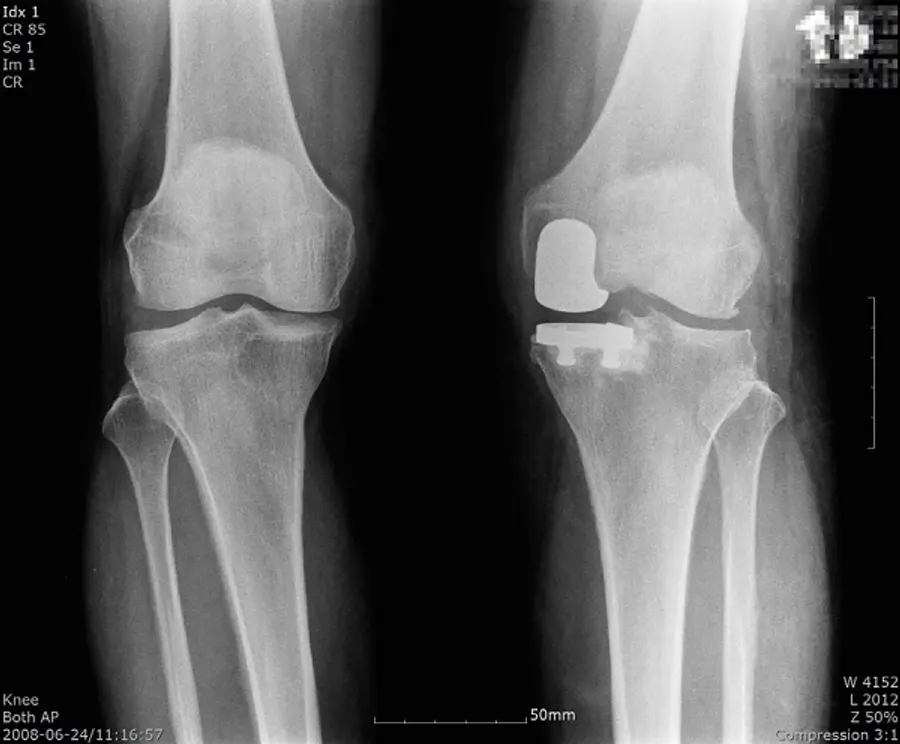

비교적 젊은 환자의 경우 관절을 최대한 보존하는 치료법을 고려해야 하는데, 무릎 관절의 일부만 절삭해 부분적으로 인공관절로 교체하는 ‘부분치환술’이나 절골술 등을 고려할 수 있다.

인공관절 부분치환술은 말 그대로 건강한 부분을 최대한 보존하는 방식이다. 건강한 관절을 제거하지 않고 살리기 때문에 기능을 보존할 수 있고, 관절 운동의 각도가 좋다는 장점이 있다.

또한 인공관절 전치환술에 비해 절개와 출혈이 적은 편이기 때문에 일상으로의 회복이 빠른 편이다. 전치환술의 경우 십자인대까지 제거해야 하는데 이 경우 균형감각, 평형 감각 등의 기능이 떨어져 계단을 오르내리는 등 감각을 유지하기 쉽지 않다는 것이 단점으로 꼽힌다. 그러나 부분치환술은 십자인대를 보존하기 때문에 평형감각을 유지할 수 있다.

다만 부분치환술을 할 수 있는 조건은 다소 까다롭다. 내측 인대의 기능이 정상이고 무릎 관절의 굴곡이 90도 이상인 환자만 고려해볼 수 있기 때문이다.